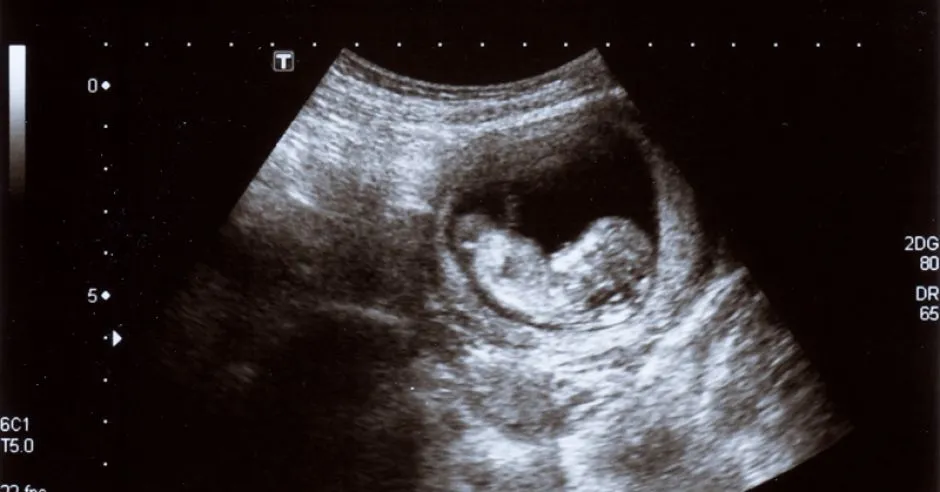

Czy wiesz, że dziecko w 7 tygodniu ciąży jest już naprawdę fascynujące? Jego wzrost następuje w niesamowitym tempie, które zaskakuje nawet doświadczonych lekarzy. Wielkość embrionu w 7 tygodniu wynosi około 1 centymetra, co można porównać do małej jagody lub pestki winogron.

W 7 tygodniu ciąży embrion przechodzi prawdziwą metamorfozę. Wygląd dziecka w pierwszym trymestrze zmienia się dosłownie z godziny na godzinę, tworząc zręby przyszłej ludzkiej sylwetki. Pojawiają się pierwsze zarysy kształtów, które będą charakterystyczne dla małego człowieka.

Najważniejsze zmiany dotyczą przede wszystkim głowy, która w tym momencie stanowi około połowy całkowitej długości ciała embrionu. Mózg rozwija się w niesamowitym tempie, tworząc skomplikowane połączenia neuronalne, które będą fundamentem przyszłych zdolności poznawczych.

Kończyny zaczynają nabierać kształtów - pojawiają się zaczątki rąk i nóg, które początkowo przypominają małe wypustki. Palce nie są jeszcze w pełni uformowane, ale już można zaobserwować ich delikatne zarysy.

Twarz embrionu również przechodzi niesamowite zmiany. Oczy, które wcześniej wyglądały jak proste punkty, zaczynają przyjmować bardziej złożoną strukturę. Powieki są jeszcze zamknięte, ale ich rozwój postępuje w bardzo szybkim tempie.